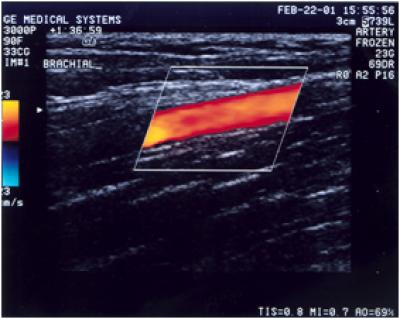

Arterial ultrasound measurements revealed that 64 percent had abnormal artery dilation in response to blood flow.

"Previous studies have shown that amenorrheic women runners have decreased dilation in the main (brachial) artery of the arm in response to blood flow," says lead author Stacy Lynch, M.D., a women's sports medicine fellow at the College. "Athletic amenorrhea has a hormonal profile similar to menopause, when the earliest sign of cardiovascular disease is reduced vascular dilation, which can limit oxygen uptake and affect performance."